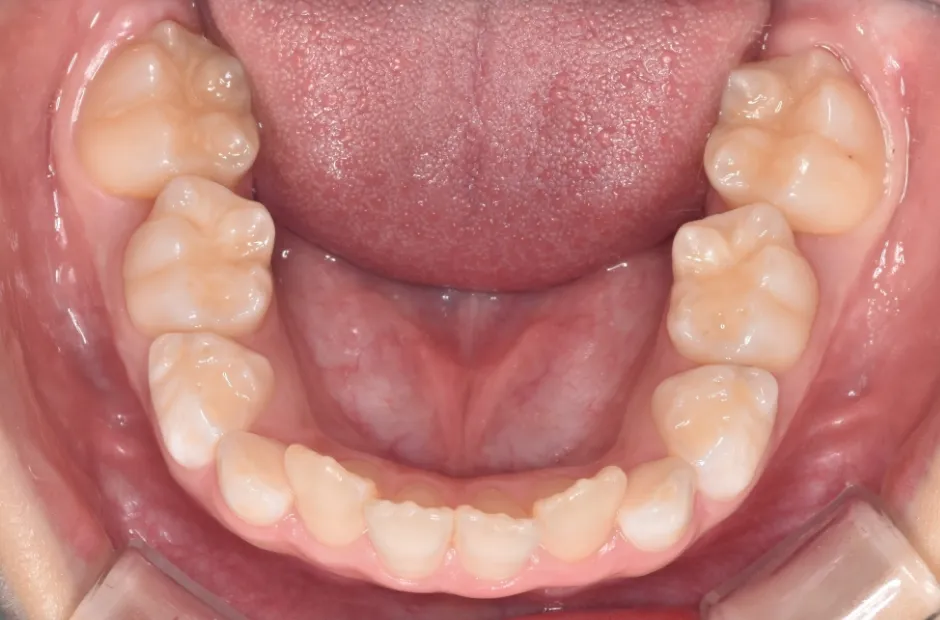

反対咬合

| 診断名・主訴 | 前歯反対咬合 |

|---|---|

| 年齢・性別 | 12歳・男性 |

| 治療期間・回数 | 1年半 18回 |

| 治療に用いた主な装置 | リンガルアーチ(前方誘導弾線) |

| 抜歯部位 | なし |

| 治療費 | 35万円(税抜) |

| リスク・副作用 | 装置による違和感・疼痛・歯肉退縮・歯根吸収・虫歯のリスクなど |

治療前

治療中

治療後